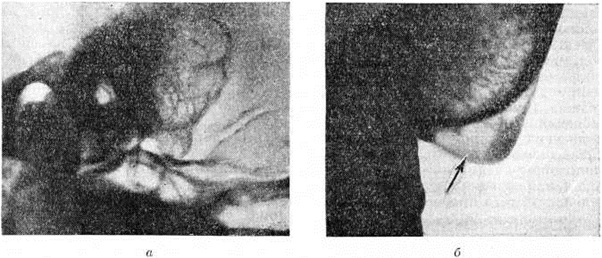

Крупная одиночная ячейка в сосцевидном отростке (относительно редкий анатомический вариант), дающая в норме на рентгенограмме интенсивное просветление, может быть принята за Мастоидит с субпериостальным абсцессом (рисунок 4). Отличить полость субпериостального абсцесса от полости, вызванной холестеатомой в сосцевидном отростке, можно по характеру их границ. Полость субпериостального абсцесса, как правило, не имеет чётких очертаний, свойственных холестеатоме (смотри полный свод знаний). В сомнительных случаях диагностика проводится только путём клинико-рентгенологическое сопоставлений. Верхушечный Мастоидит (абсцесс Бецольда) может быть легко пропущен, если сделать одну боковую рентгенограмму височной кости (рисунок 5, а). При толстой наружной пластинке коркового вещества сосцевидного отростка костный дефект внутренней пластинки на боковом снимке не обнаруживается. На снимке в косой проекции по Стенверсу дефект этой пластинки выявляется чётко (рисунок 5, б). Для распознавания верхушечного Мастоидит очень важен учёт клинические, симптомов, определяющих тактику рентгенолога. Симптом полости рентгенологически нередко обнаруживается и при замаскированных Мастоидит при лечении антибиотиками. Рентгенологические наблюдение показывает, что консервативное лечение Мастоидит при благоприятных исходах ведёт к полной костной регенерации полости абсцесса и восстановлению воздушности сохранившихся ячеек. Серийное послойное рентгенологическое исследование височной кости таких больных указывает на замещение дефекта нормальной костной тканью (рисунок 6, а, б) и перестройку сосцевидного отростка, тип строения которого из распространённого пневматического становится смешанным спонгиозно-пневматическим. Рентгенологические наблюдения указывают на длительность этого процесса (1 — 2 года).